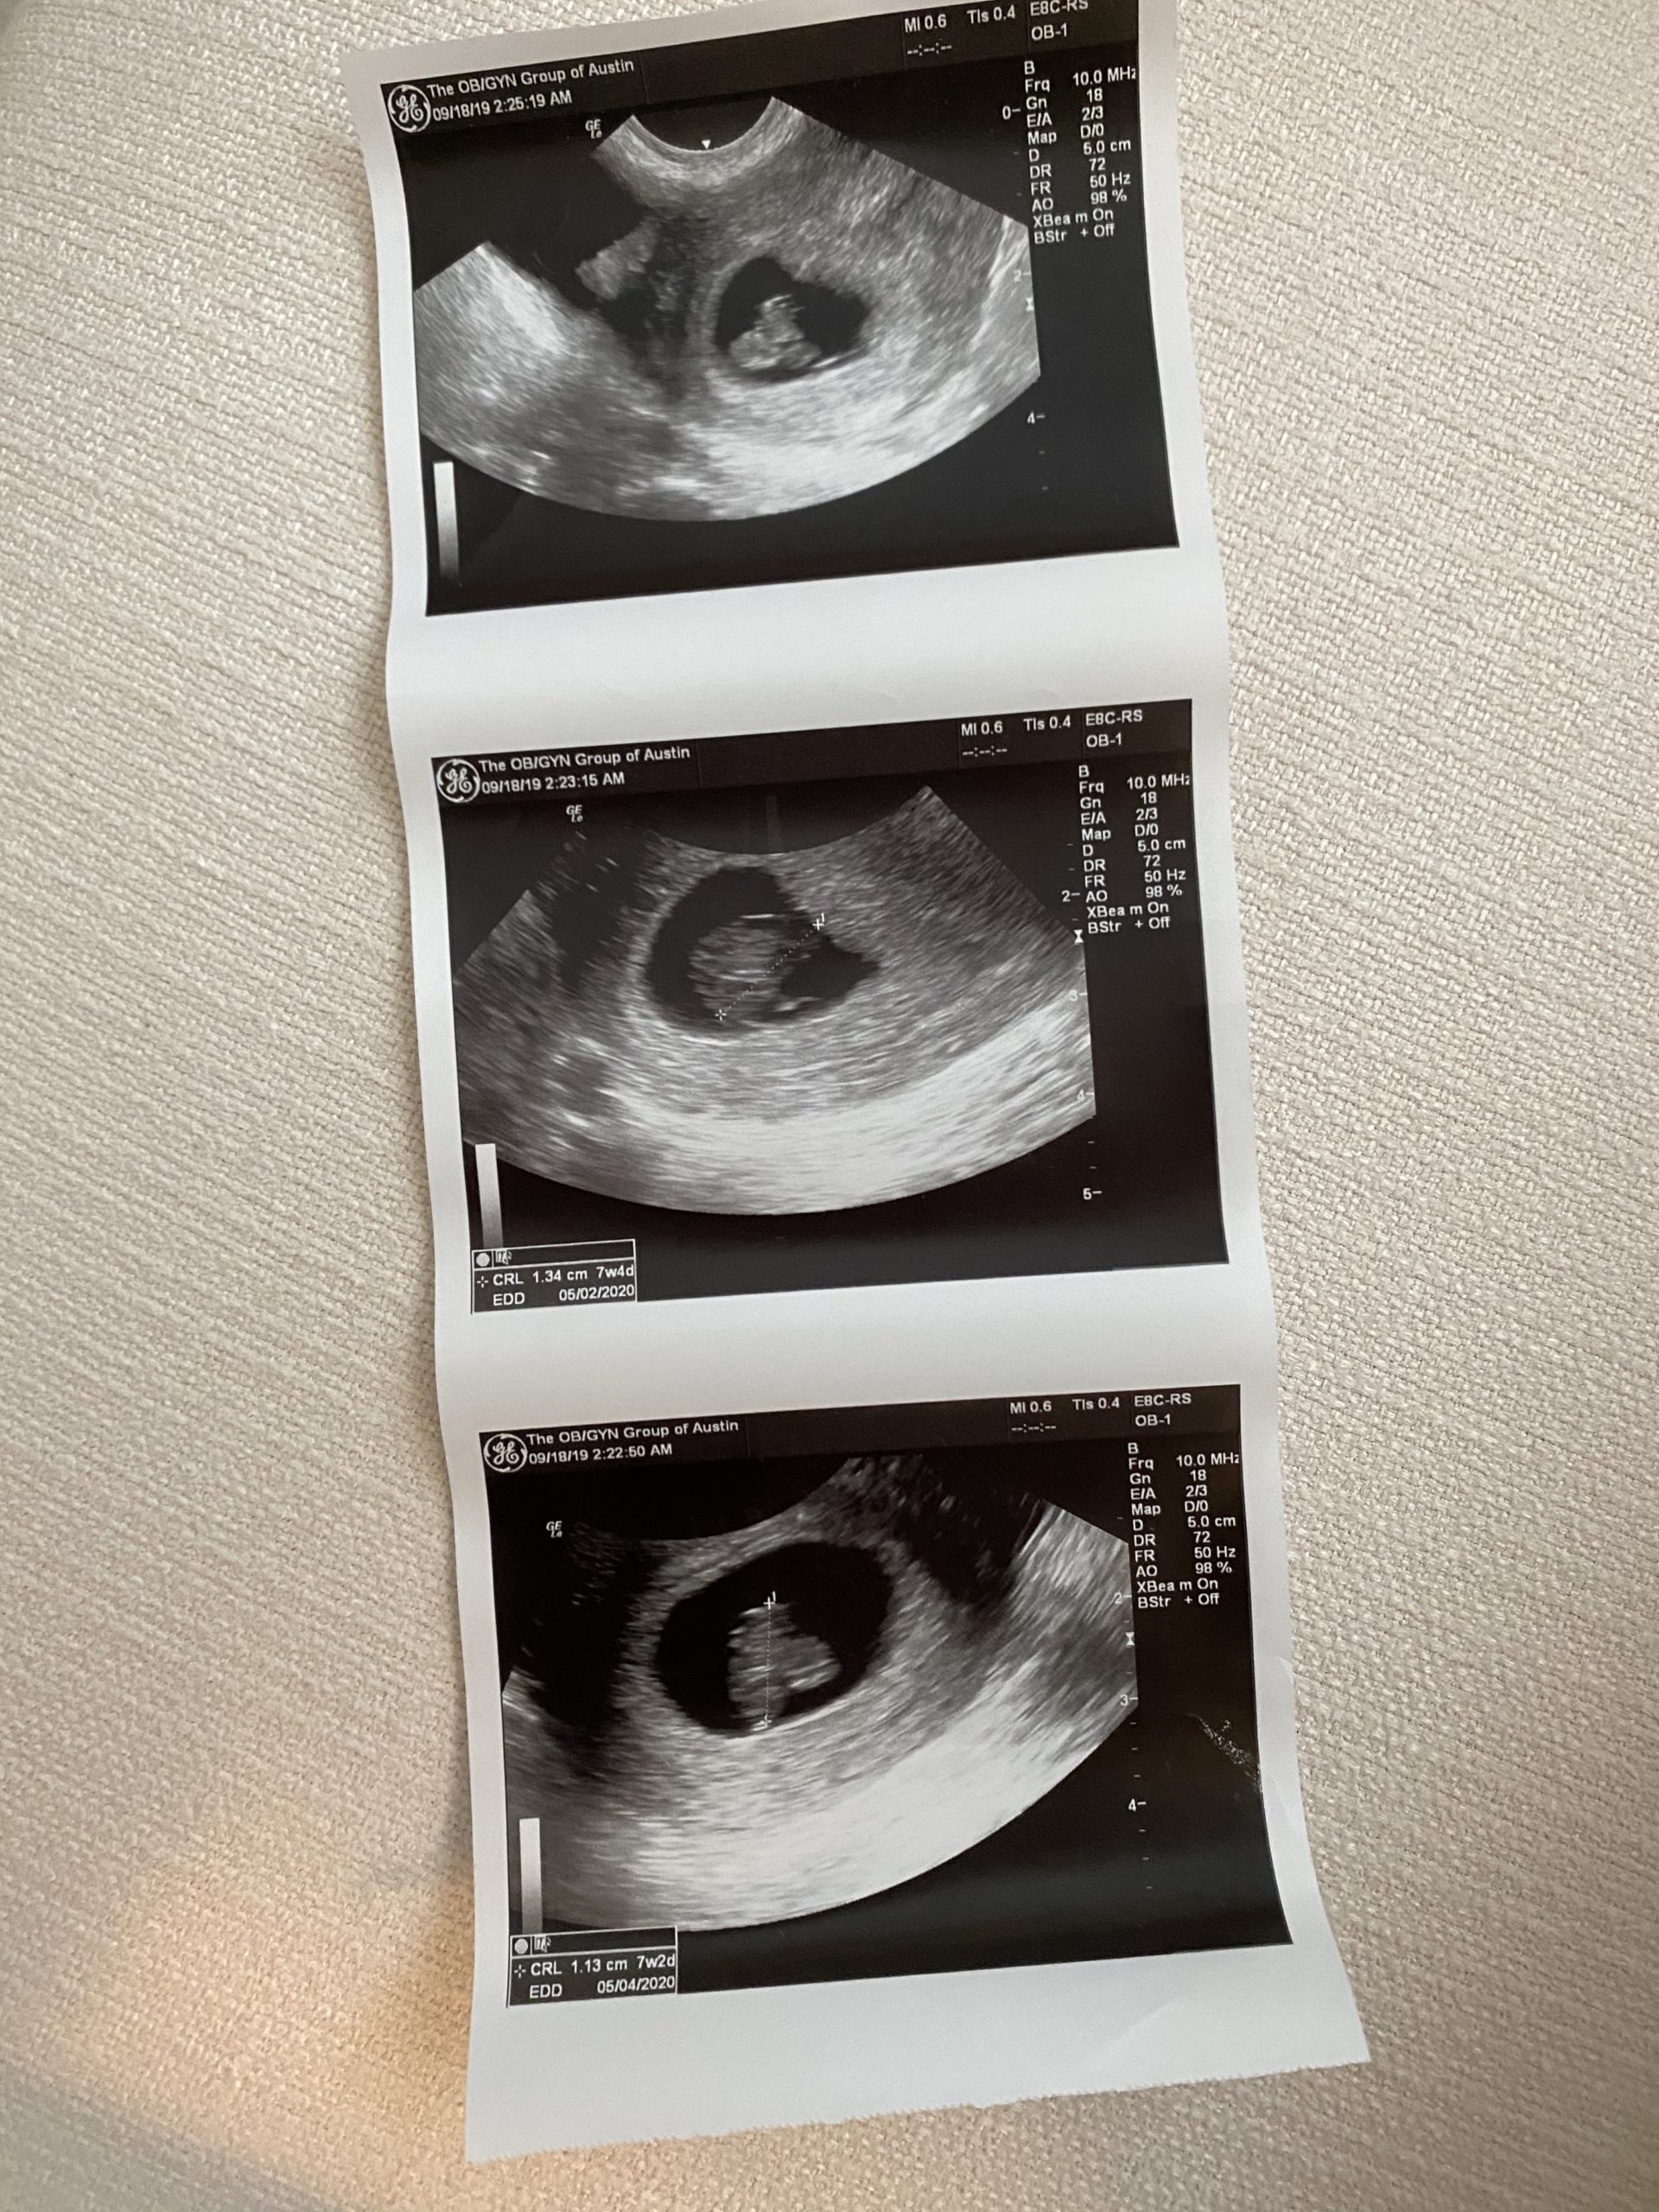

Bébé’s first photos!

The First Sonogram

Finally, at seven weeks and few days pregnant we got to see the doctor. I gave a urine sample and they did a vaginal sonogram. We got to see the little shrimp like cluster and hear that super fast heart beat. We got our first photos to bring home and made an appointment for the following week to see the doctor.

It was really nice after all that waiting to finally get some tangible confirmation that I was indeed pregnant. I am just one of the those people who really needs to see it to believe it, haha. The following week, we saw our doctor again for what is considered the first actual appointment. There the doctor and her nurse walked us through all the forms and what to expect, how often we’d see the doctor, etc etc. There was another sonogram and more pictures.